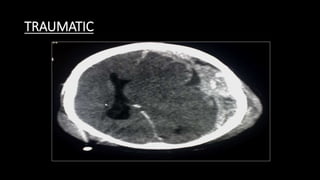

TRAUMATIC